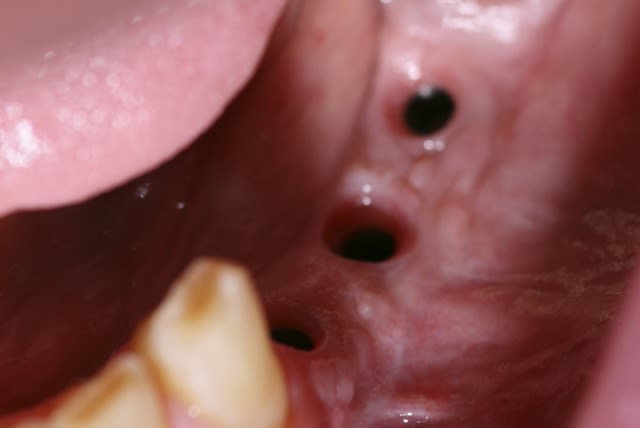

image 12 et 13: réouverture, forage et pose des implants ( les implants ont été posés par le DR A. L dans le 31)

image1 réouverture et dépose du matériel ( du tissu fibreux s'est insinué dans les fentes mésiales et distales que j'ai du cureter)

image2 pose d'une membrane pour faire une ROG sur ces dites fentes

image 3 réentrée à 3 mois

image4 pose des implants + re ROG autogène)

image 5 vis de cicat ( re 2mois )

image6 visualisation de la cicat gingivale 6 semaines après la pose des vis de cicat.

désolé pour les photos merdiques et je n'ai pas de photos de la prothèse.